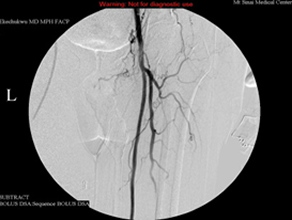

This 75-year-old man’s primary care doctor referred him to my clinic because of left leg cramps after ambulating a few blocks and I found that his left superficial femoral artery was occluded (left column images). Using catheters, wires, balloons, and a covered stent, I restored blood flow through the blocked artery and his problem resolved (right column images).